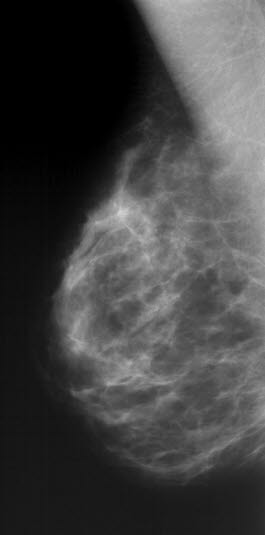

Mammografi er en røntgenundersøkelse som framstiller brystvevet slik at forandringer som kan være uttrykk for brystkreft, lar seg avbilde. Kreftsvulster mindre enn 1 cm kan vanligvis ikke påvises ved rutinemessig undersøkelse av brystene utført av kvinnen selv eller legen.

Røntgenbildet viser kjertler, melkeganger og bindevev mot en bakgrunn av fett. Ved typiske forandringer kan røntgenlegen skille godartet fra ondartet forandring. Mens godartede forandringer skyver normalt brystvev tilside når de vokser, kan ondartede forandringer vokse inn i omliggende brystvev. Utseende av svulsten og forkalkninger kan også gi viktig tilleggsinformasjon. Tidligere røntgenbilder av brystene er verdifulle til sammenligning når røntgenlegen vurderer de nye bildene. Supplerende ultralyd kan være avklarende, og gjøres som regel dersom det er spesifikke forandringer eller spesielle grunner til mistanke som ligger bak ønsket om undersøkelsen.

Det normale brystvevet endres med alderen fordi kjertelvevet etter hvert forsvinner og fettmengden øker. Det er stor variasjon i det mammografiske utseende av normale bryst. De fleste ondartede forandringer kan påvises ved mammografi, men som ved andre diagnostiske undersøkelser hender det at noe overses eller ikke er synlig på bildene. Det er derfor viktig å utføre egenkontroll av brystene, også etter en mammografiundersøkelse. Hvis noe er mistenkelig, skal andre typer undersøkelser vurderes (se under). Det er liten strålefare med undersøkelsen.